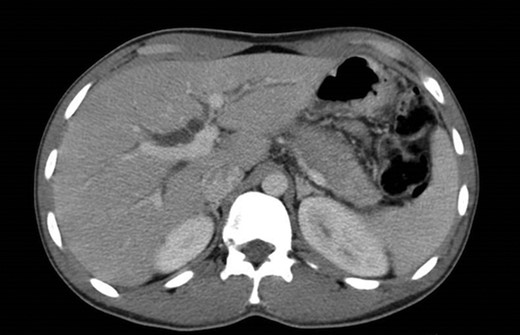

The abdominal exam revealed a soft, non-distended, non-tender abdomen, without any palpable masses, organomegalies or lymphadenopaties. Blood chemistry showed a cholestatic pattern: bilirubin 6.61 mg/dl, alkaline phosphatase 434 U/l, gamma-glutamyl transpeptidase 374 U/l, alanine transaminase 542 U/l and aspartate transaminase 228 U/l. Lipase, amylase and complete blood count showed regular values. Abdominal ultrasound revealed dilatation of the intra and extrahepatic bile ducts and the pancreas was enlarged and hypoechoic, compatible with inflammation. CT scan was performed to discard a neoplastic obstruction and confirmed an intrahepatic biliary ductal dilatation (Fig. 1) and a dilatation of the distal bile duct with no luminal lesions (Fig. 2).

Pancreatic CT scan. Dilatation of the distal bile duct, with no evidence of luminal lesions nor a pancreatic mass constricting the bile duct (endoluminal prosthesis).